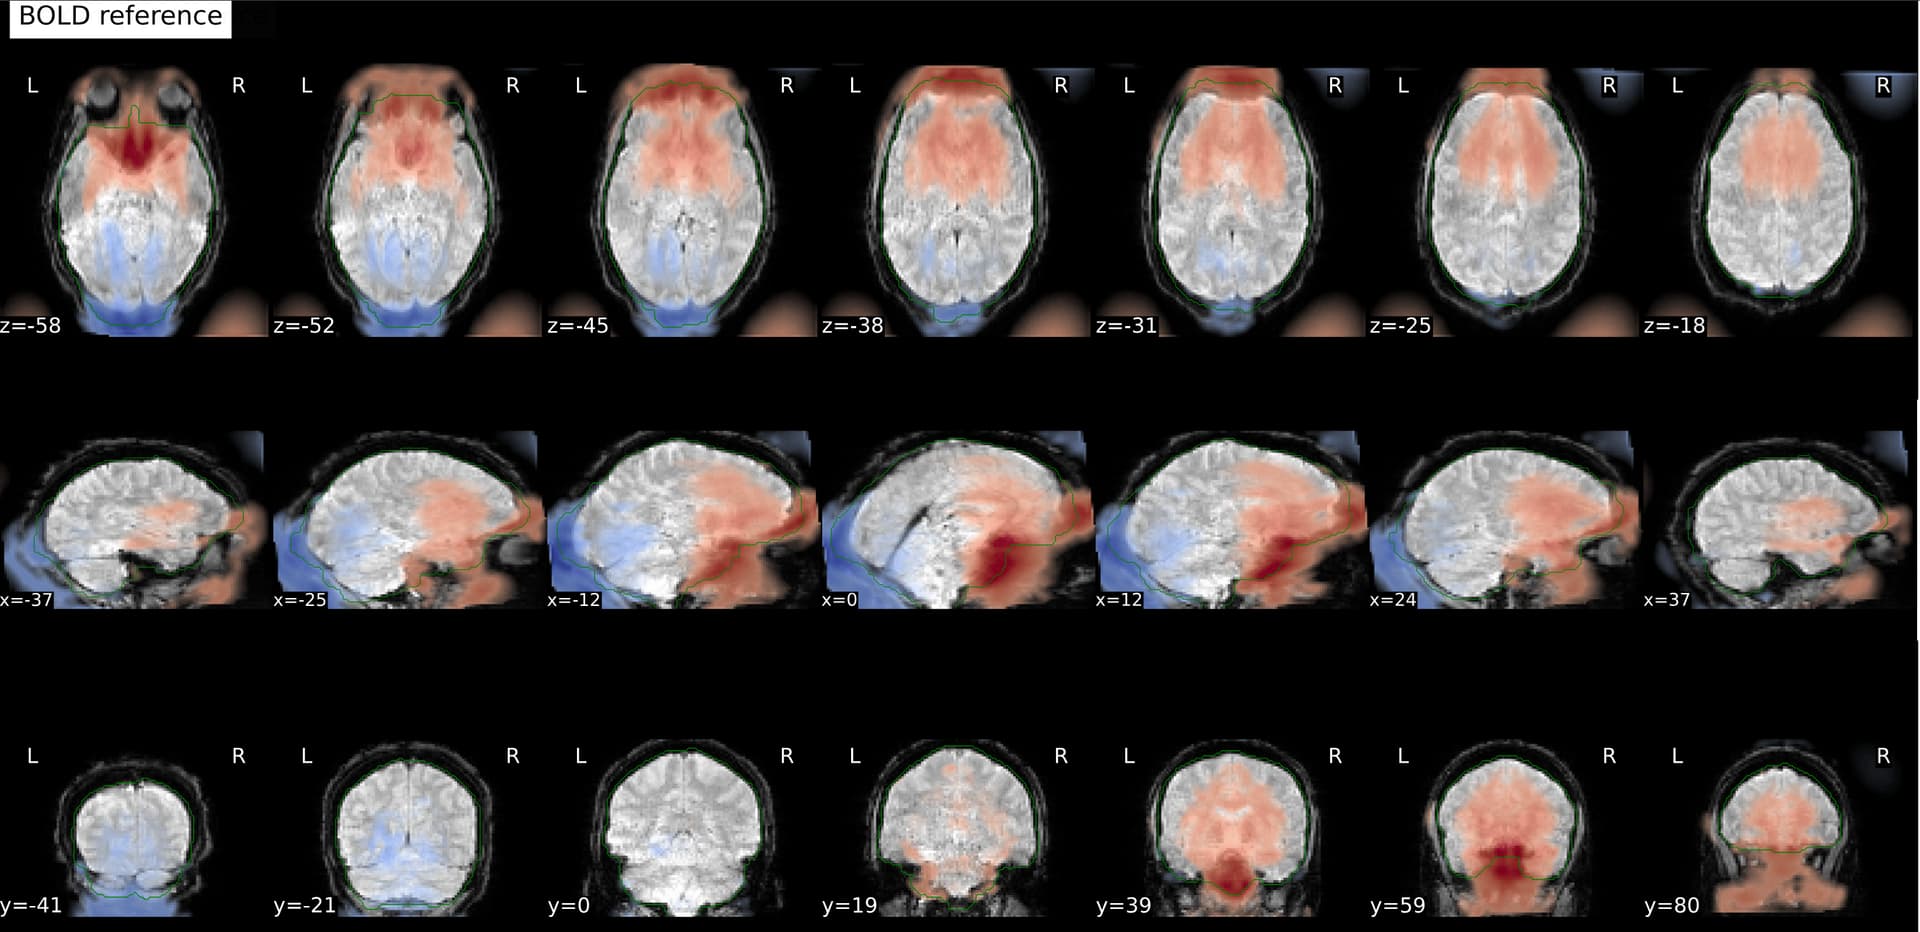

And these are the fmapCoreg_bold images: